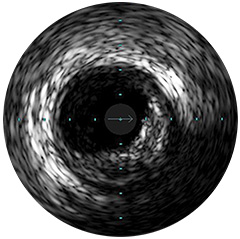

Einführung der völlig neue Anwendungsplattform IntraSight von Philips – Zusammenspiel von Bildverarbeitung, Physiologie, Koregistrierung und Software für eine optimale Patientenversorgung. IntraSight bietet eine umfassende Palette klinisch bewährter Modalitäten wie iFR/FFR, IVUS und Koregistrierung* für einfachere komplexe Interventionen, schnellere Routineverfahren und eine verbesserte Patientenversorgung.

IntraSight ist auf Basis einer intelligenten, anwendungsbasierten Plattform konzipiert, die sich bei neuen verfügbaren Anwendungen und Modalitäten an die sich ändernden Anforderungen Ihres Labors anpassen lässt – und das ohne neue Hardware erwerben zu müssen. Nur IntraSight von Philips bietet Ihnen erstklassige Bildverarbeitungs- und Physiologie-Tools mit iFR, iFR-Koregistrierung*, FFR, IVUS, IVUS-Koregistrierung* und Angio+*. Dank seiner modularen Architektur bleibt IntraSight über die neuesten Entwicklungen und wichtigen Sicherheitsupdates auf dem Laufenden.

Digitale IVUS- Bildverarbeitung

Abbildung 2